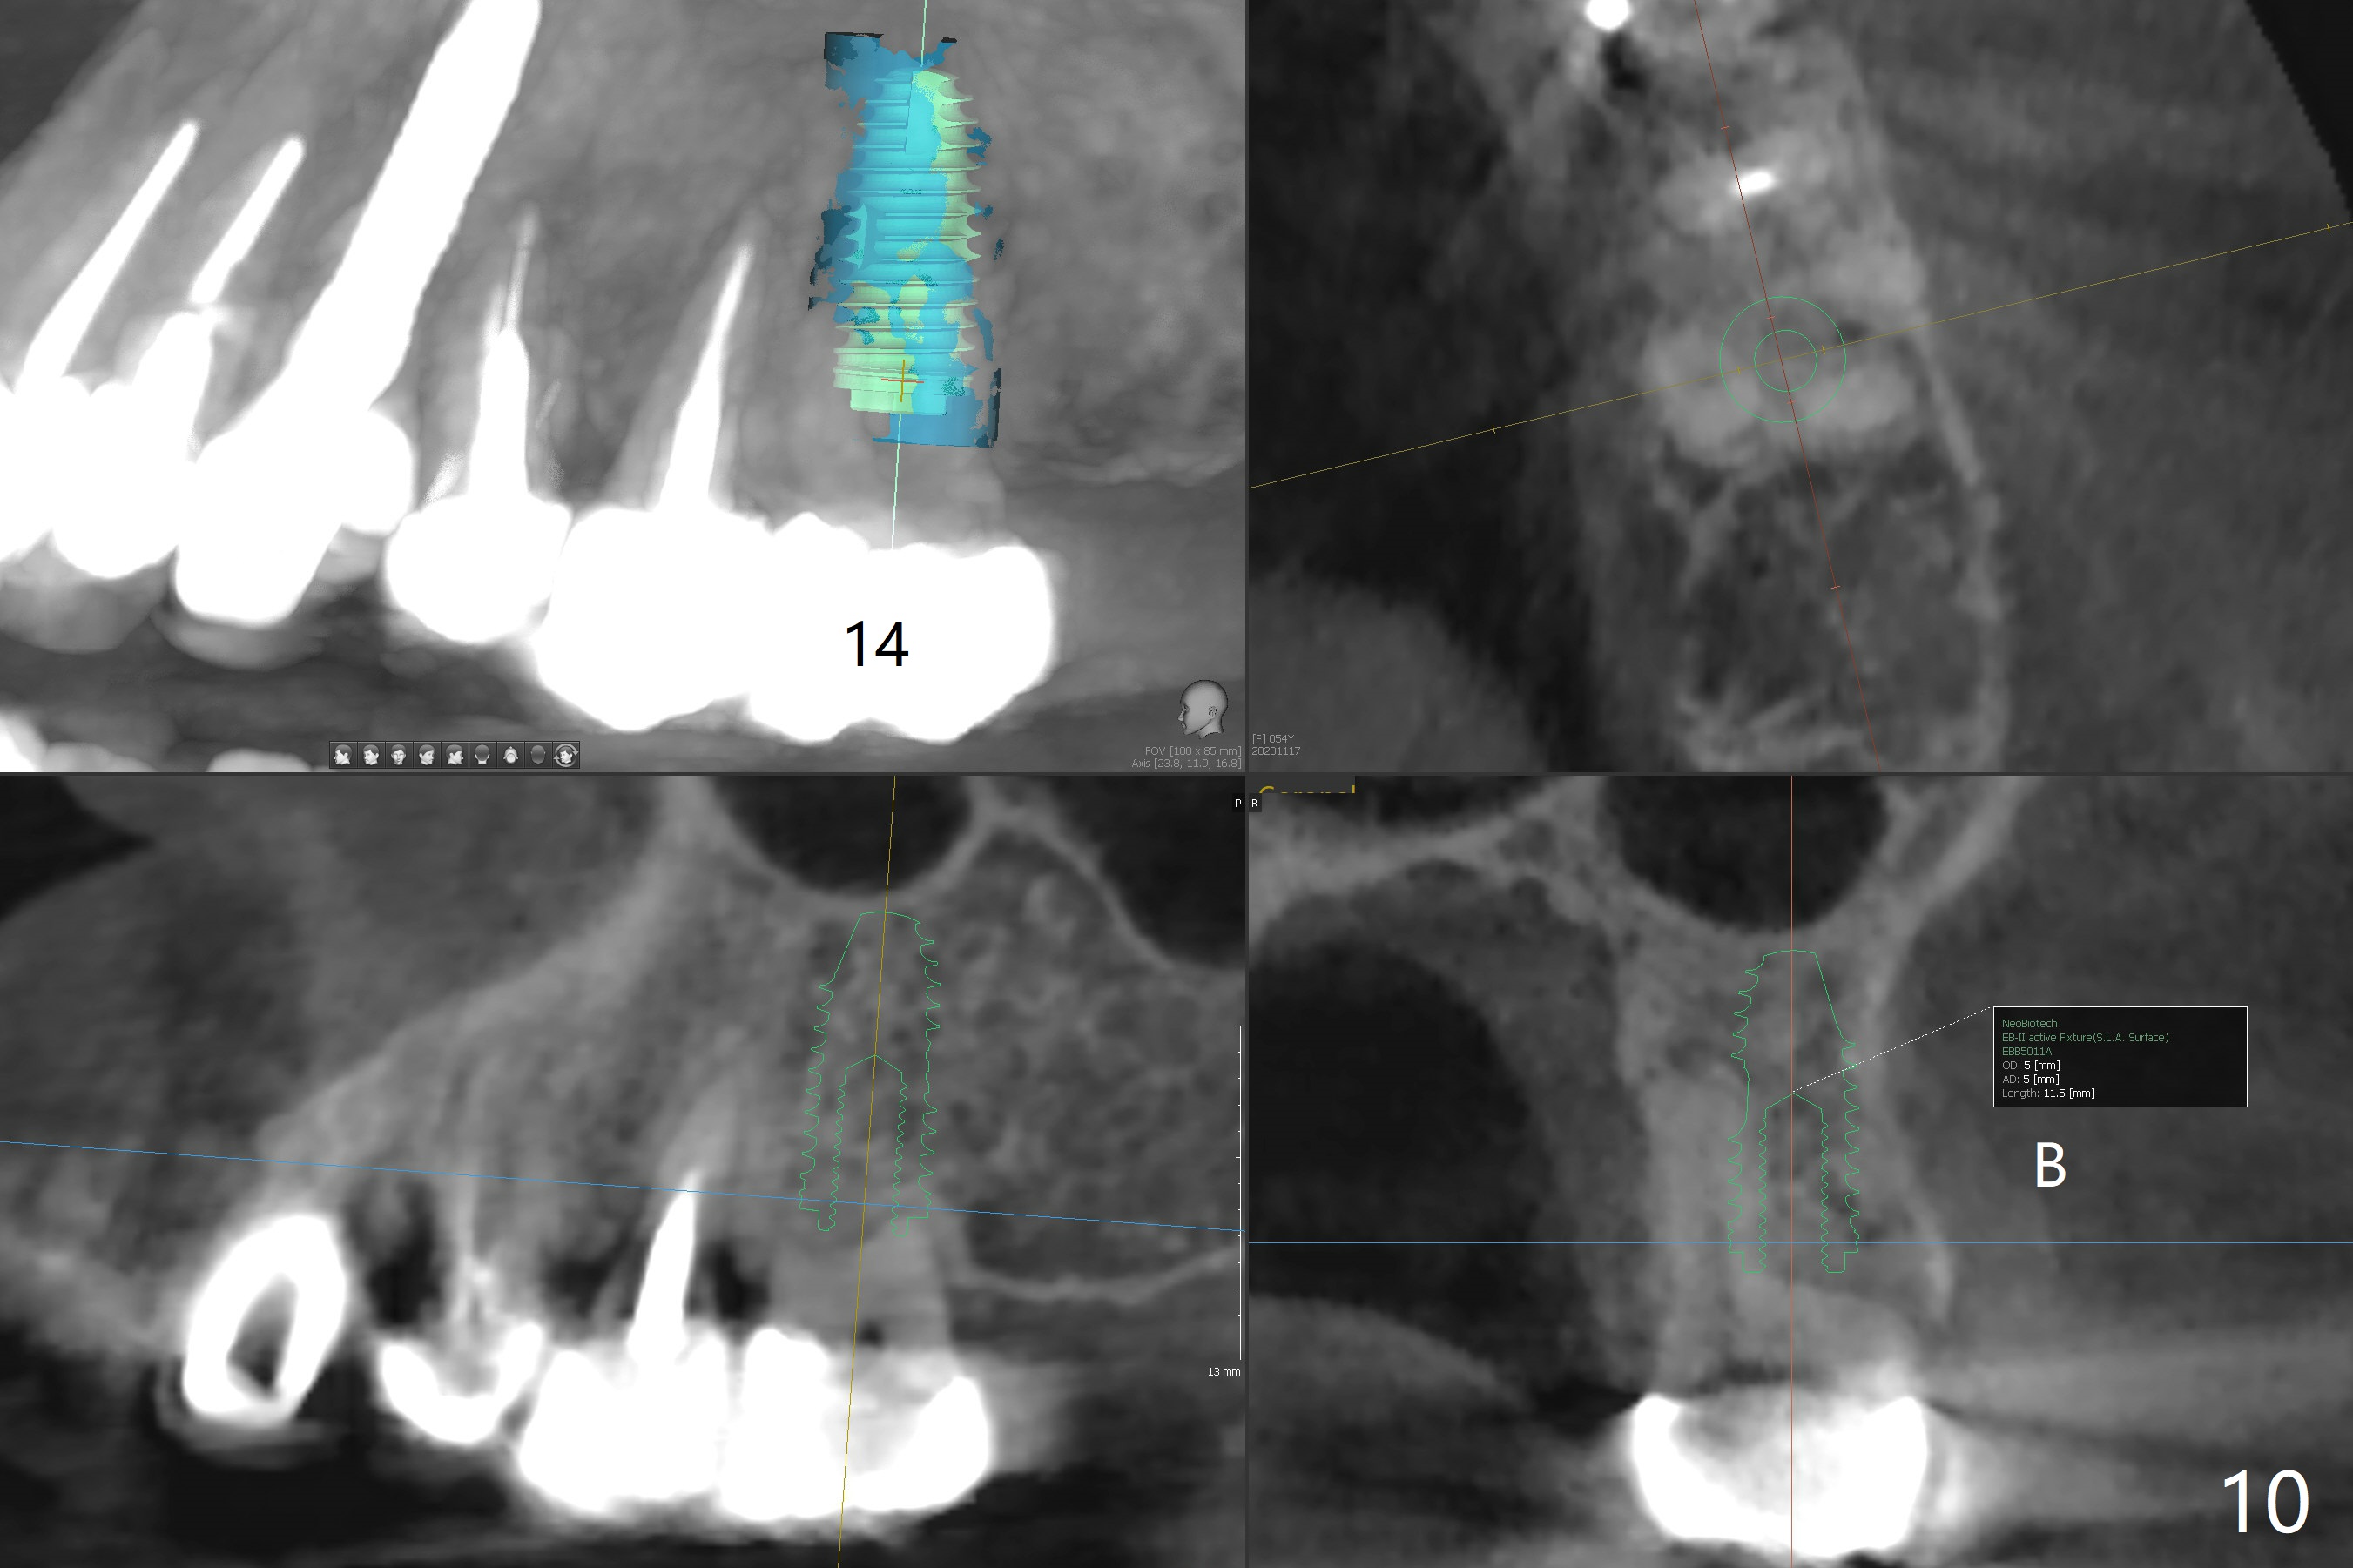

A 53-year-old woman wants to extract the tooth #3 with recurrent apical periodontitis (Fig.1). Socket preservation is conducted (Fig.2). The tooth is terminal in the arch and difficult to keep periodontal or acrylic dressing in place. To overcome the situation, a prefabricated space maintenance is placed without cementation because of its inherent fitness (Fig.3). Periodontal dressing (Fig.4 D) appears to be retained in place. The spacer is lost prematurely due to no cement, but the wound appears to be healing 13 days postop (Fig.5,6). The socket heals 3 months postop (Fig.7,8). However the ridge is narrow 19 months postop (Fig.9, as compared to that of the tooth #14 (Fig.10)).